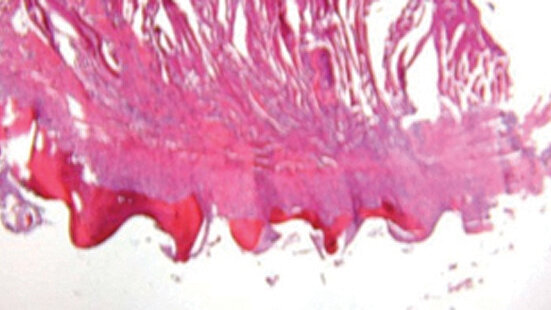

Another anatomical misconception with placement of MDIs is the ability during placement to perforate the lingual or buccal plates of bone and/or the cortical bone in the floor of the sinus or nasal cavity. This is not factual. The 3M ESPE MDI is neither designed nor capable of advancing itself through cortical or Type 1 (D-1) bone.